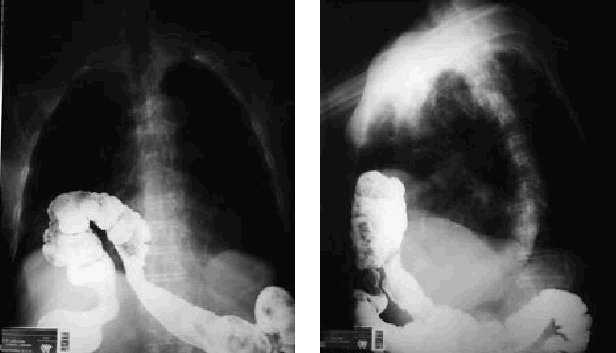

Varón de 89 años de edad, con antecedentes de síndrome prostático y cardiopatía no filiada, que ingresó por síndrome anémico intenso que precisó la transfusión de varios concentrados de hematíes. En la analítica solicitada se detectó ferropenia grave como dato de interés. Dado el estado de deterioro general del paciente, no se pudo realizar endoscopia digestiva alta, por lo que se le practicó seriada esofagogastroduodenal que puso de manifiesto la presencia de hernia de hiato con importante reflujo gastroesofágico. Para completar el estudio se practicó un enema opaco, que objetivó como hallazgo casual la introducción del ángulo hepático del colon en la cavidad torácica a través del orificio diafragmático anterior derecho (figs. 1 y 2) como consecuencia de la presencia de una hernia de Morgagni.

El diafragma constituye un tabique muscular que separa la cavidad abdominal de la torácica. Cuando esta función fracasa, parte del contenido abdominal pasa al tórax y se producen las hernias diafragmáticas. La hernia de Morgagni se produce a través del foramen del mismo nombre, que es un defecto en la parte anterior del diafragma en la región costoxifoidea. Se trata de hernias directas con un saco peritoneal bien definido; en la mayoría de los casos, el contenido es colon transverso y epiplón. El estómago también puede ascender atraído por el epiplón gastrocólico, pero no es lo más frecuente. Asimismo, el intestino delgado se ha visto en alguna ocasión. La mayoría de los casos se dan en el lado derecho. Estas hernias son raras (representan el 3% de las hernias diafragmáticas) y suelen aparecer de forma predominante en individuos obesos y en mujeres. Acostumbran a ser un hallazgo casual tras la realización de una radiografía de tórax o de un enema opaco, ya que por lo general son asintomáticas, aunque pueden manifestarse como molestia epigástrica, dispepsia, distensión abdominal o clínica respiratoria. En algunos casos se auscultan borborigmos en el tórax. Los síntomas agudos casi siempre se deben a obstrucción del intestino grueso, aunque también pueden incarcerarse el epiplón y el estómago. Los síntomas y su gravedad dependen del volumen de contenido intestinal que pasa al tórax y de la estrangulación. En lactantes las hernias grandes pueden afectar la ventilación y hacer necesaria una corrección quirúrgica inmediata. En adultos está indicada la observación y, en caso de estrangulación, el tratamiento es quirúrgico.